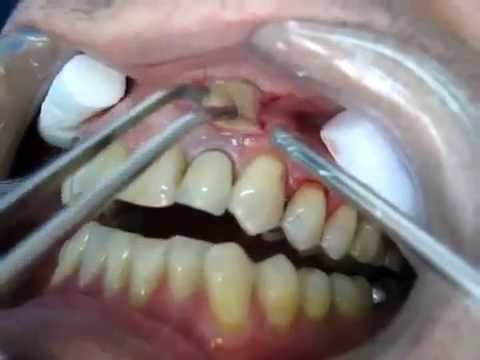

Un Dentiste perce un Abcès Dentaire oO ! Attention aux âmes sensibles !!! :

comment soulager un abcès sur la gencive